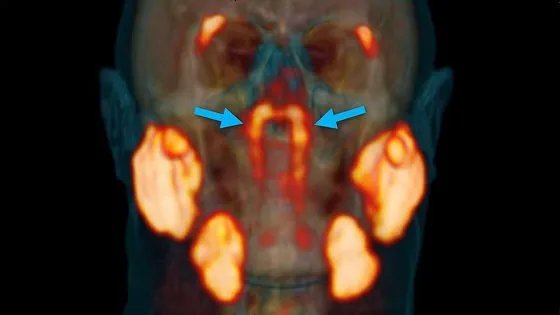

那么唾液腺是如何被生物学家发现的呢?这就要从对癌细胞的研究说起了,研究人员起初是想通过一种放射性示踪剂进入人体后与前列腺癌细胞中的蛋白质结合,从而标记癌细胞,对这个示踪剂进行扫描就可以得到癌细胞所处的位置。就在追踪的过程中,发现了在人体的唾液腺中也存在了标记点,除了标记癌细胞的位置之外,也让研究人员意外的发现了这个新的器官“管状腺”。更加关键的是,这个新发现的器官并不是少数人特有的,经过对多名实验者的检测,发现这个器官是人体的标配,而且它并不是一个没有用的组织。

在原本的癌细胞研究中,这一新发现提供了很大帮助,尤其是有头颈部癌症患者在接受放射性治疗的时候,放射性疗法损伤的不仅是癌细胞,也有唾液腺以及其他正常的细胞,由此就会造成很严重的并发症,在这之前有很多案例,癌症患者在接受治疗一段时间后,会出现吞咽或说话方面的困难,这就是因为唾液腺受到了损伤。而对这一位置治疗越多,器官受损伤就越严重。